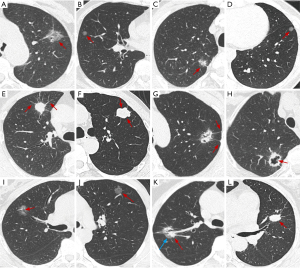

CT radiological features

Figure 2 displays the pathological results corresponding to different SPN lesions, and Figure 3 provides examples of qualitative features in CT images. Inter- and intrareader agreement analyses for all CT imaging features demonstrated excellent consistency (all Cohen’s κ and ICC >0.8). As shown in Table 2, statistically significant differences (P<0.01) were observed between Group A and Group B in the training and testing datasets for pulmonary nodule imaging characteristics, including maximum diameter, density type, shape, spiculation, pleural retraction, lobulation, and air bronchogram, while there were no significant differences in other features. Except for density type, no statistically significant differences (P>0.05) were found in imaging characteristics between the training cohort and external testing cohort.